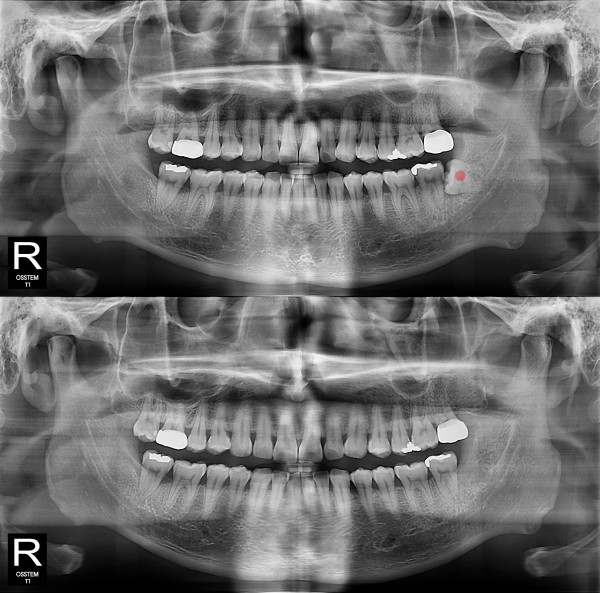

사랑니발치 완전 매복 사랑니

ae27575af29d49719312fde5a1f0cca6_1764402576_9324.jpg